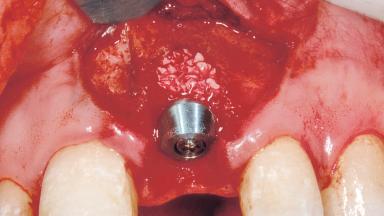

Immediate Placement of an Implant in a Maxillary Left Central Incisor Site

A 33-year-old female patient presented with an upper left central incisor that required extraction after a failed endodontic therapy. The tooth had been traumatized when the patient was a teenager and had undergone several endodontic treatments, including two apicectomy procedures. The patient was in good health and did not smoke. Clinical examination showed that the patient had a high lip line. In full smile, the gingival margins of the upper teeth were visible to the first molars. The gingival margins of central incisors 11 and 21 were only just showing. Examination of tooth 21 confirmed that the tooth was mobile and had hypererupted by 1 mm.

Bone Augmentation Horizontal|Simultaneous

Augmentation Materials Xenogenous|Membrane

Soft Tissue Grafting Simultaneous

Placement Protocol Immediate implant placement

Tooth Site Maxillary incisor or canine